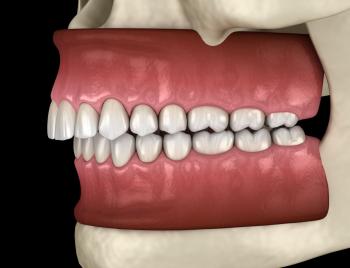

The Foundation: Surgeons remove one of the patient's teeth—often a canine—along with a portion of the surrounding jawbone and ligament. This tooth-bone unit is then meticulously sculpted and a tiny, custom optical lens is inserted into its center.

The Window to the World: This "tooth-lens" complex is then implanted into the eye. Over time, the body’s own tissues integrate with the tooth and bone, creating a stable, living framework that holds the new lens securely in place. Because the tooth is made of the patient's own tissue, the body does not reject it—a common problem with artificial implants.